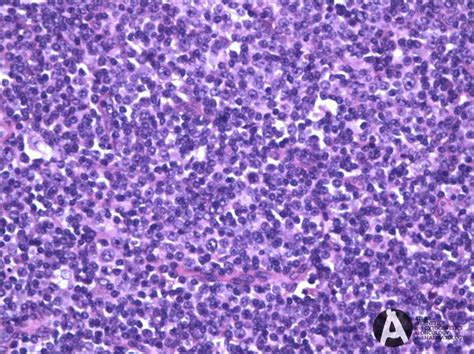

Now, if you’re experiencing any of these symptoms, it’s super important to see a doctor. They’ll start with a physical exam to check for swollen lymph nodes and ask about your medical history. If they suspect lymphoma, they’ll likely order a lymph node biopsy. This involves removing a small piece of the lymph node and examining it under a microscope. This is the gold standard for diagnosing NMZL because it allows pathologists to identify the specific abnormal B-cells. In addition to the biopsy, doctors might order blood tests, such as a complete blood count (CBC) and a comprehensive metabolic panel, to assess your overall health and look for any abnormalities. Imaging tests, like CT scans or PET scans, can help determine the extent of the lymphoma and whether it has spread to other parts of your body. Bone marrow biopsies might also be performed to check if the lymphoma has infiltrated the bone marrow. All these tests together help provide a complete picture of your condition, enabling doctors to stage the lymphoma accurately.